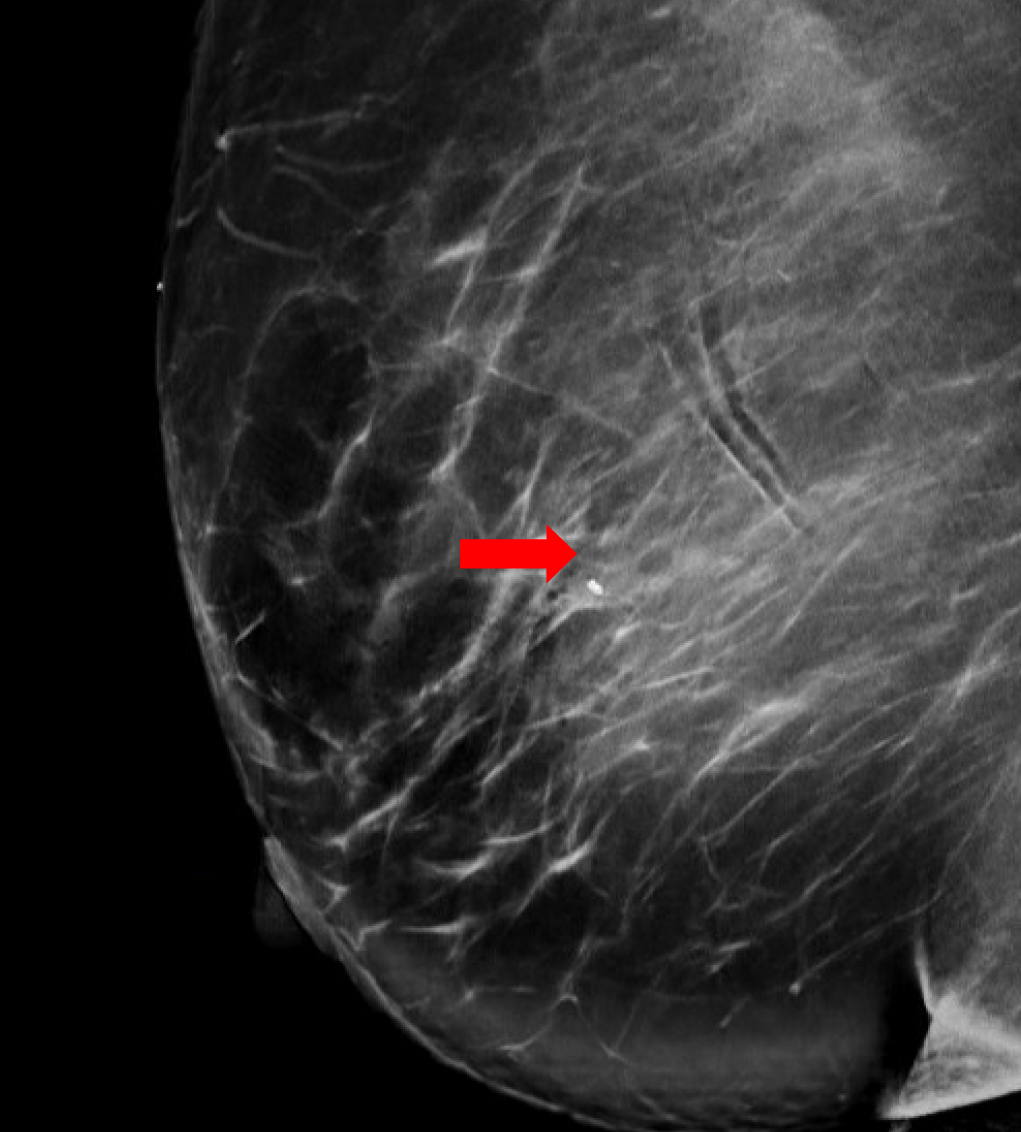

Se trata de una mujer premenopáusica de 46 años, sin antecedentes médicos o quirúrgicos, que acudió inicialmente a la clínica de cirugía mamaria después de que su mamografía anual de cribado descubriera una masa mamaria derecha no palpable de 0,6 x 0,8 x 0,7 cm a las 11 horas (oc), a 1 cm del pezón (FTN) (Figura 1). Se sometió a tres mamografías de detección previas sin ningún hallazgo notable. La mamografía de tamizaje se declaró no concluyente (BI-RADS 0) y se completó una ecografía mamaria con hallazgos similares. Una conversación más detallada con la paciente reveló que se había observado una secreción sanguinolenta en el lado derecho de su sostén en los últimos meses, pero no había otras preocupaciones o síntomas. Ante los hallazgos imagenológicos no concluyentes, se decidió realizar una mamografía diagnóstica para una valoración más específica (Figuras 2a y 2b) tras una biopsia con aguja gruesa guiada por ecografía y la colocación de un clip de localización para el diagnóstico tisular (Figura 3). La anatomía patológica reveló un papiloma intraductal con hiperplasia ductal y una metaplasia apocrina sin atipia. Dada su continua secreción sanguinolenta del pezón, hubo preocupación por posibles células premalignas subyacentes (discutidas más adelante); Por lo tanto, se recomendó que la paciente se sometiera a una mastectomía parcial. La masa permanecía inpalpable; por lo tanto, se colocaría un Savi Scout justo antes de la intervención operativa para ayudar a localizar el área de interés.

Figura 3. Localización y biopsia guiadas por ecografía de la masa mamaria en cuestión, observada por primera vez en una mamografía de detección. La imagen posterior a la biopsia incluye los cambios tisulares típicos que se observan una vez que se realiza una biopsia con aguja gruesa (marca de hash).